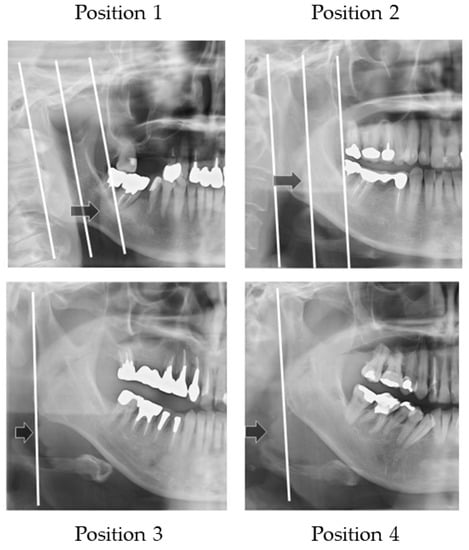

2.4.4. Width of Tongue

Figure 6 illustrates how to evaluate the outer position of tongue and Figure 7 shows sample images. The width of tongue was assessed according to the location where the outer border of tongue overlapped the anatomical structure. If the right side and left side of the outer border of the tongue were different, the inner position side was used.

Figure 6.

Width of the tongue. The location where the outer border of tongue overlapped the anatomical structure was assessed.

Figure 7.

Sample images of width of tongue. Arrows show the outer border of the tongue.

Three landmarks were defined, as follows:

- The distal border of the mandible line is a simulated line, which is defined between the posterior point of the mandibular condyle and posterior point of the angle of the mandible.

- The mesial border of the mandible line is defined as the line that is the distal border line moved in parallel to the coronoid process.

- The midline of the border of the mandible line is defined as the midline of the distal border of the mandible line and the mesial border of the mandible line.

The outer border of tongue is defined according to the following positions:

Position 1: Observed between the mesial border of the mandible line and the midline border of the mandible line;

Position 2: Observed between the midline of border of the mandible line and the distal border of the mandible line;

Position 3: Observed on the distal border of the mandible line;

Position 4: Observed outside of the distal border of the mandible line.